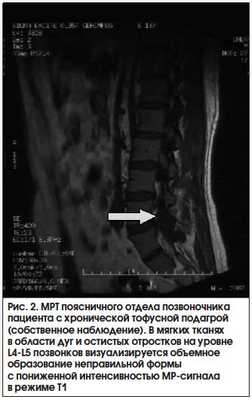

Основное значение для визуализации мягкотканных тофусных масс, прежде всего при их атипичном расположении, имеет МРТ. Наиболее информативными являются режимы Т1 и Т2. В режиме Т1 тофусы выглядят как однородные области с сигналом промежуточной или низкой интенсивности, в режиме Т2 изображения тофусов также характеризуются различной интенсивностью сигнала, которая может быть как гомогенно высокой, так и низкой. Причина, по которой интенсивность сигнала варьируется, может меняться в зависимости от содержания жидкости в тофусе: в случае острого воспалительного процесса, при значительном количестве жидкостного содержимого в формирующемся, воспаленном тофусе отмечается высокая интенсивность сигнала, а при малом количестве жидкости и большом числе кристаллов моноурата натрия, кальцификации тофуса, развитии фиброза, в результате хронического воспаления, обусловленного кристаллами моноурата натрия, или при отложении гемосидерина - низкая [16, 33, 34]. На рисунке 2 представлена МРТ пациента с подагрой.